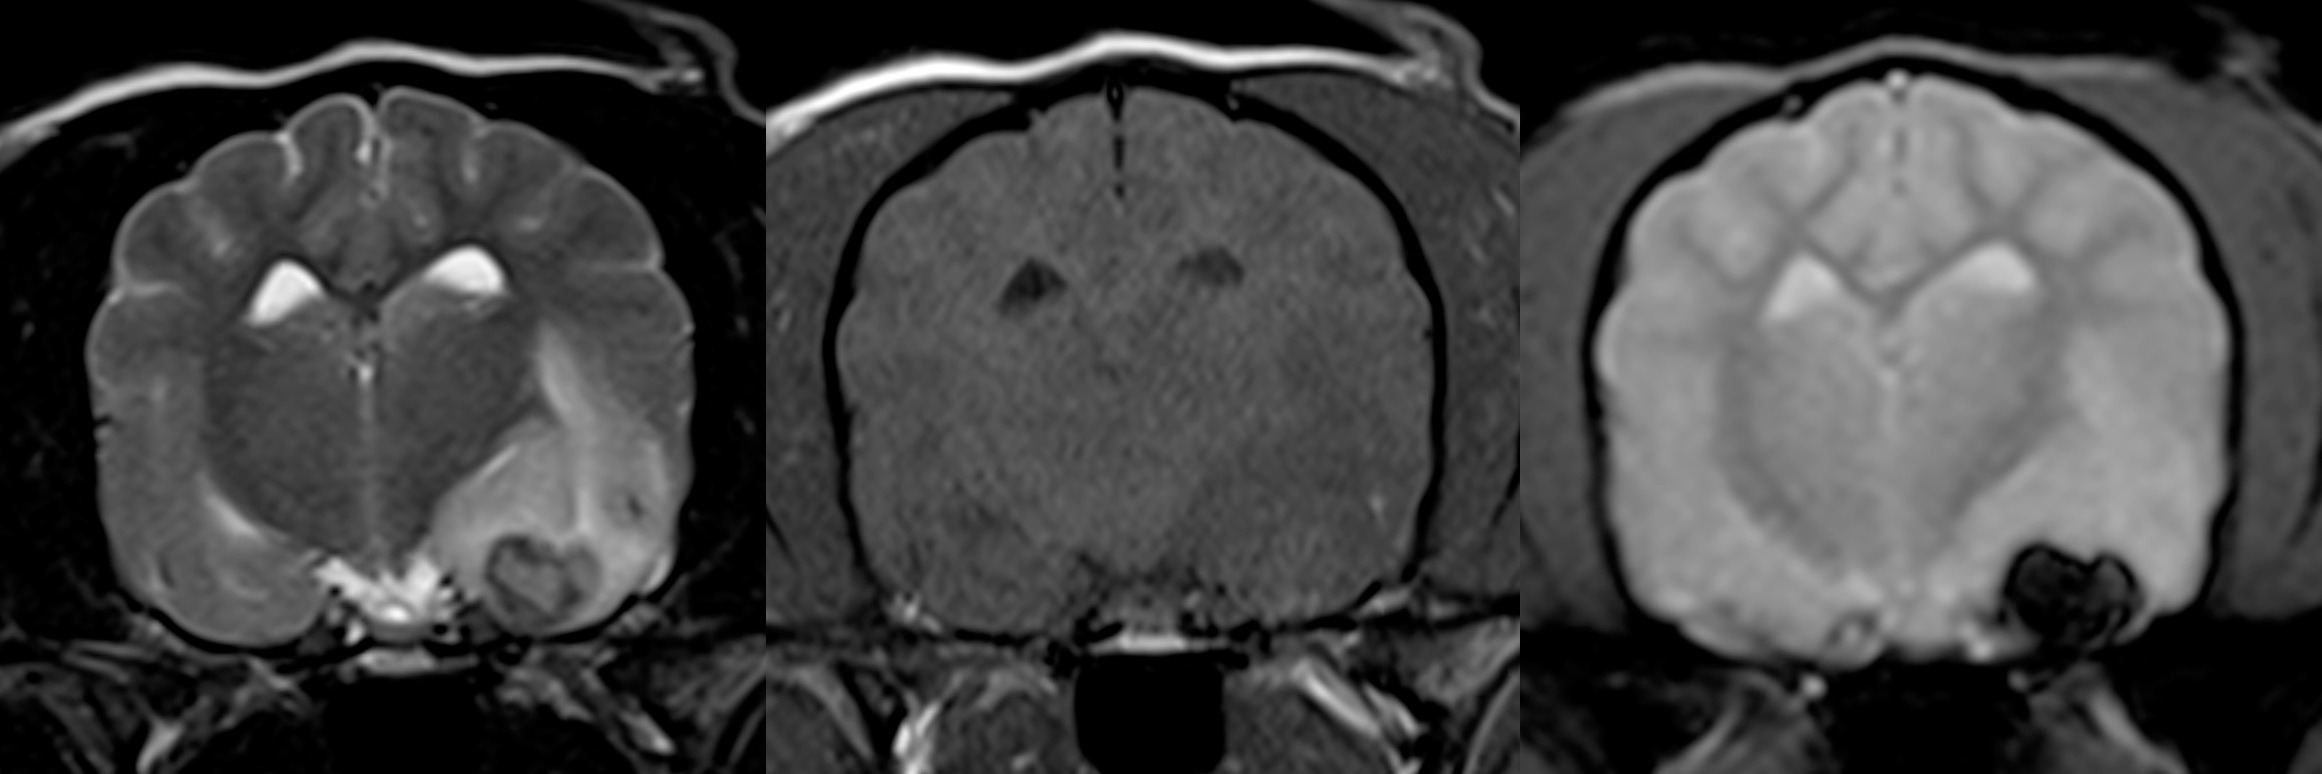

Quelle démarche diagnostique lors d’AVC ?

L’imagerie par résonance magnétique (IRM) est la technique de choix pour identifier un accident vasculaire cérébral (AVC) : 1 – Vrai 2 – Faux Si vous avez coché Vrai, c’est la bonne réponse 😁 Un accident vasculaire cérébral (AVC), bien connu des propriétaires et parfois appelé « attaque cérébrale » ou « infarctus… Lire la suite